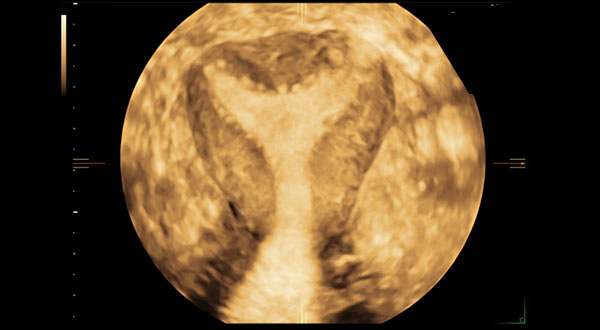

Adénomyose : problématique de la prise en charge

VolusonTM France, GE HealthCare